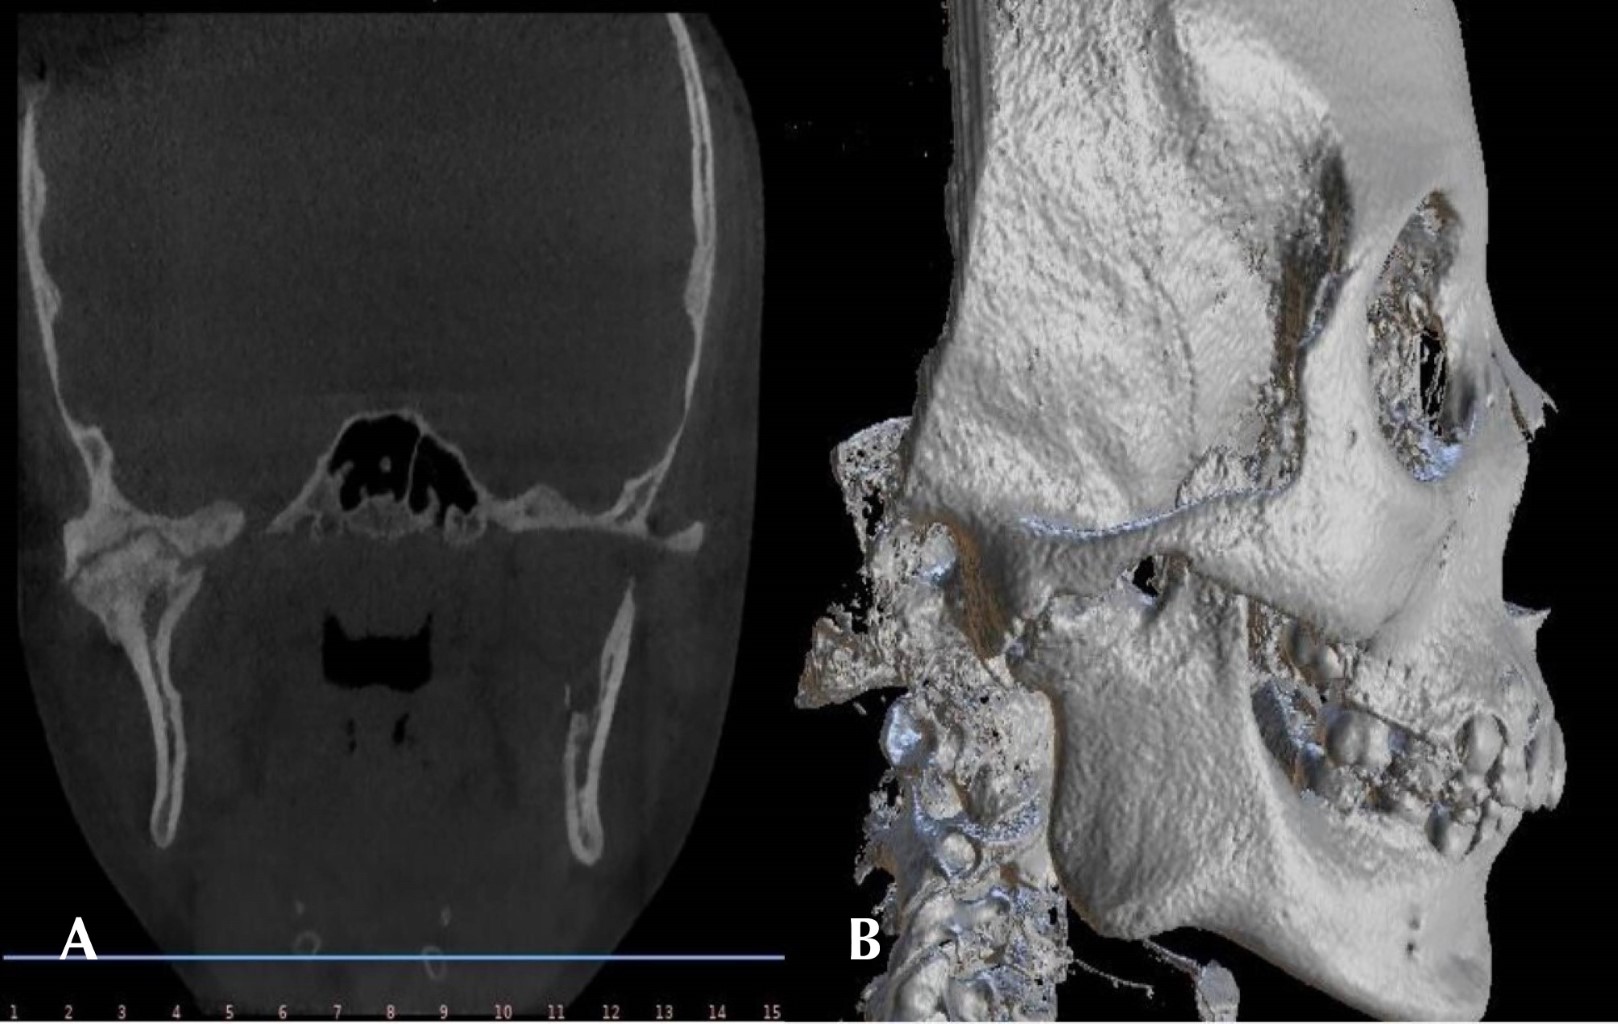

Se presenta paciente femenino de 10 años, al interrogatorio la madre refiere iniciar padecimiento actual al caer de una altura aproximada de dos metros a la edad de cinco años, ocasionando anquilosis de la articulación con disminución de la apertura bucal. Al examen clínico la madre negó alergias, comorbilidades y uso de medicamentos. Extraoralmente no se observaron signos de asimetría facial, a la exploración física e intraoral se encontró trismo severo, apertura bucal de 1 mm, dificultades masticatorias, maloclusión e higiene oral deficiente. Se realizó una tomografía computarizada donde se observa masa anquilótica que afecta la articulación temporomandibular derecha compatible con el tipo 2 de la clasificación de Shawney (Figura 1).

La muestra se envía a estudio histopatológico el cual reporta ser compatible con anquilosis mandibular. Al año de evolución el resultado es satisfactorio, la paciente presenta una apertura bucal de 30 mm sin recidivas. Radiográficamente no se observan datos de reanquilosis mandibular (Figura 3). Debido a limitaciones económicas, la paciente no pudo continuar con el seguimiento del tratamiento.